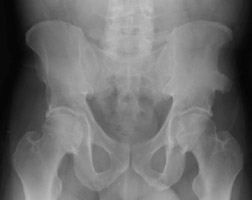

- Click on the image for a larger versionAAP radiograph of the pelvis. This demonstrates a prior avulsion of the right anterior superior iliac spine. The avulsed fragment has healed with some deformity to the iliac wing.